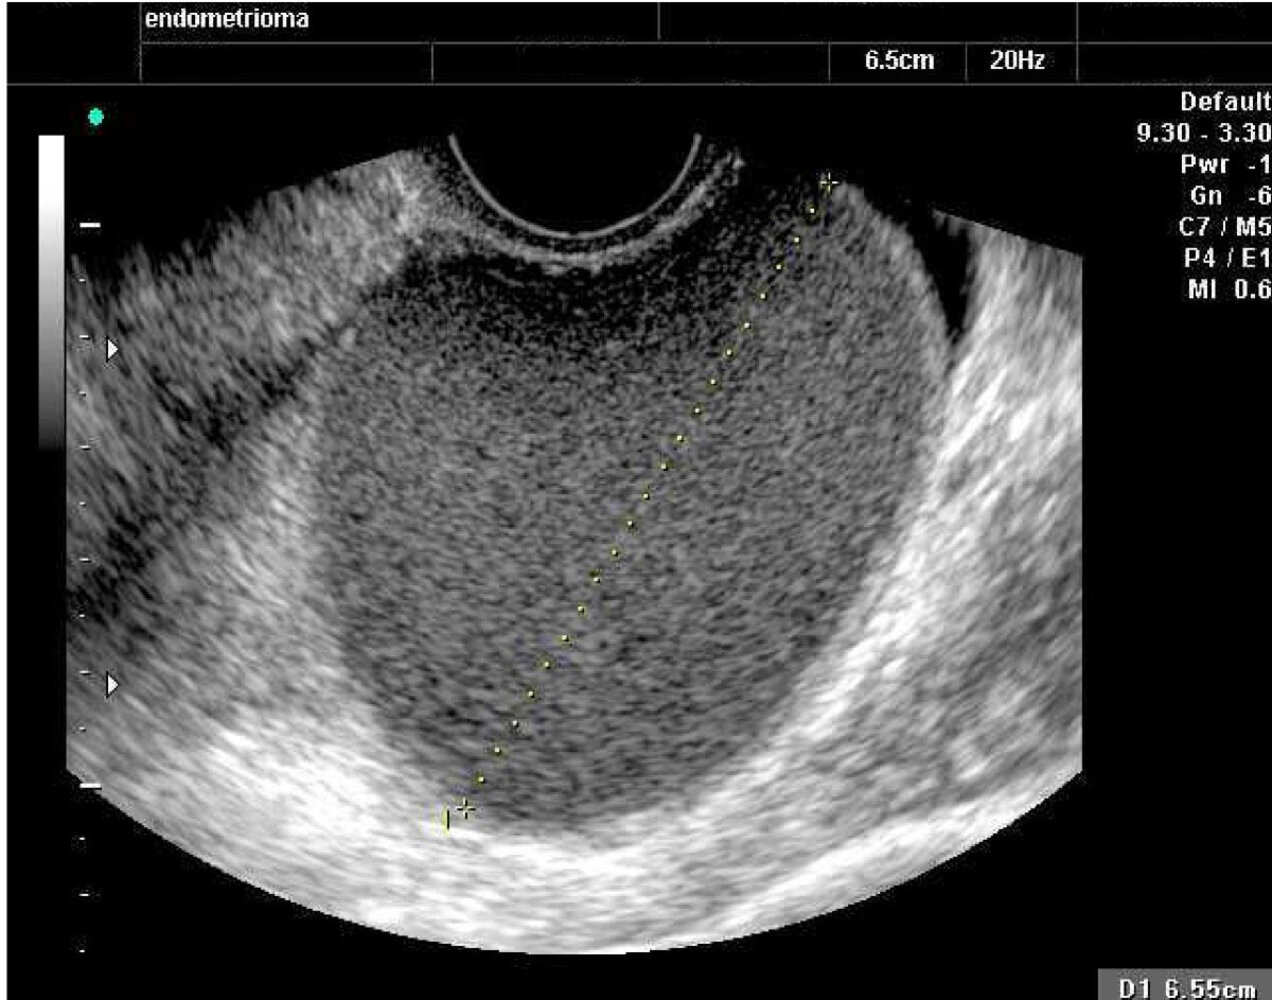

Transvaginal ultrasound

• Ovaries: Performed to diagnose ovarian cysts, tumors, and follicular maturation

• Uterus

• Myometrium (e.g., to diagnose leiomyomas)

• Endometrium

• Echogenic layer in the long axis view of the uterus (referred to as the ā€œendometrial stripeā€)

• Endometrial thickness varies with the menstrual cycle

• Postmenopausal women with an endometrial thickness greater than 8 mm should undergo a follow-up ultrasound after 1–3 months

• Postmenopausal women with an endometrial thickness greater than 10 mm should undergo hysteroscopy and endometrial curettage to rule out endometrial carcinoma.

• Assessment of fetal development during the first trimester

• Measurement of cervical length in cases of cervical incompetence